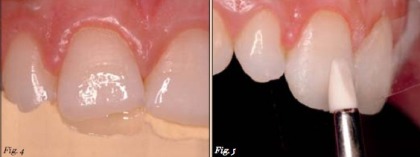

Trường hợp này, nha sĩ quyết định sử dụng hệ thống phục hồi composite của IPS Empress (Ivoclar Vivadent). Vật liệu được đặt từng lớp sử dụng khóa silicone được làm từ trước. Khóa silicone cho phép tái tạo lại hình dạng giải phẫu của răng tự nhiên nhất có thể (Hình 4). Để tạo được sự chuyển màu dần dần trên răng, nha sĩ sử dụng màu men A1 để làm tăng độ sáng và hiệu ứng quầng ở 1/3 phía rìa cắn của răng và tạo ra vùng trong mờ rõ. Màu ngà A2 và A1 để tạo thùy múi.

Một phần vật liệu được kéo dài đến rìa men nhằm che dấu sự chuyển tiếp giữa răng thật và miếng trám.Các đường rãnh giữa các thùy múi được lấp kín bằng Trans Opal. Cuối cùng, miếng trám được phủ 1 lớp mỏng Trans 30. Lớp này cũng mở rộng đến rìa men (Hình 5).

Hình 4: Composite được đắp từng lớp sử dụng khóa sicone làm hướng dẫn.

Hình 5: Bề mặt được tạo hình theo hình dạng mong muốn trước khi composite được trùng hợp.